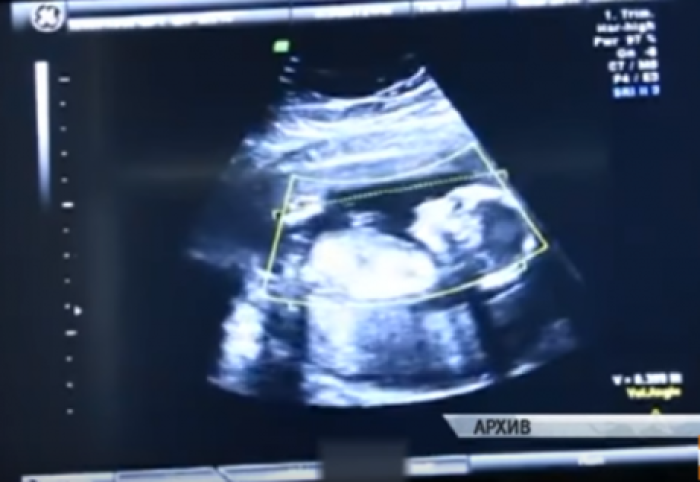

Во март 2017 година, жена се пријавила во болница во Барнаул во Западен Сибир. Била во 41 недела од бременоста, а до тогаш ниту еднаш не посетила доктор или бабица. Причината била недоверба кон целата медицинска индустрија.

По прегледот, докторите откриле нешто шокантно.

Жената имала вонматерична бременост која е навистина опасна по животот на трудниците и плодот. Жената веднаш била однесена на операција.

Кога хирургот го извадил бебето се случило чудо, тоа било живо и немало никакви последици, а било тешко 4 килограми.